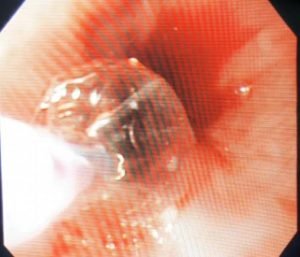

بعض النصائح الطبية عند استخدام مناظير الجهاز الهضمي لتركيب دعامة معدنية في الجزء السفلي للمرئ وفتحة الفؤاد لعلاج عدم القدرة على بلع الطعام والشراب لحالة تعاني من ورم سرطاني في الجزء السفلي للمرئ مسبباً ضيق سرطاني شديد في الجزء السفلي للمرئ وممتد إلي فتحة الفؤاد ، وفي بعض الحالات مثل هذه الحالة قد نحتاج لعمل توسيع للجزء الضيق بإستخدام بالونة التوسيع قبل تركيب الدعامة وذلك لنجاح عملية تركيب الدعامة وللحصول على أفضل النتائج، ويجب عمل هذا التوسيع بحرص ودقة لعدم حدوث نزيف أو أي مضاعفات. ويجب متابعة المرضي واستكمال علاج المرضي بعد ذلك.

Upper Gastrointestinal Endoscopy with Successful deployment of Partially Covered Antireflux Self Expandable Metallic Stent (SEMS) for treatment of Absolute Dysphagia from malignant Lower Esophageal Stricture Extending to the Cardia (Esophageal Carcinoma).

Balloon dilatation of the tight stricture was cautiously done at first, avoiding bleeding and other complications, to facilitate Successful Stent Deployment and better results. Follow up is essential for further management.